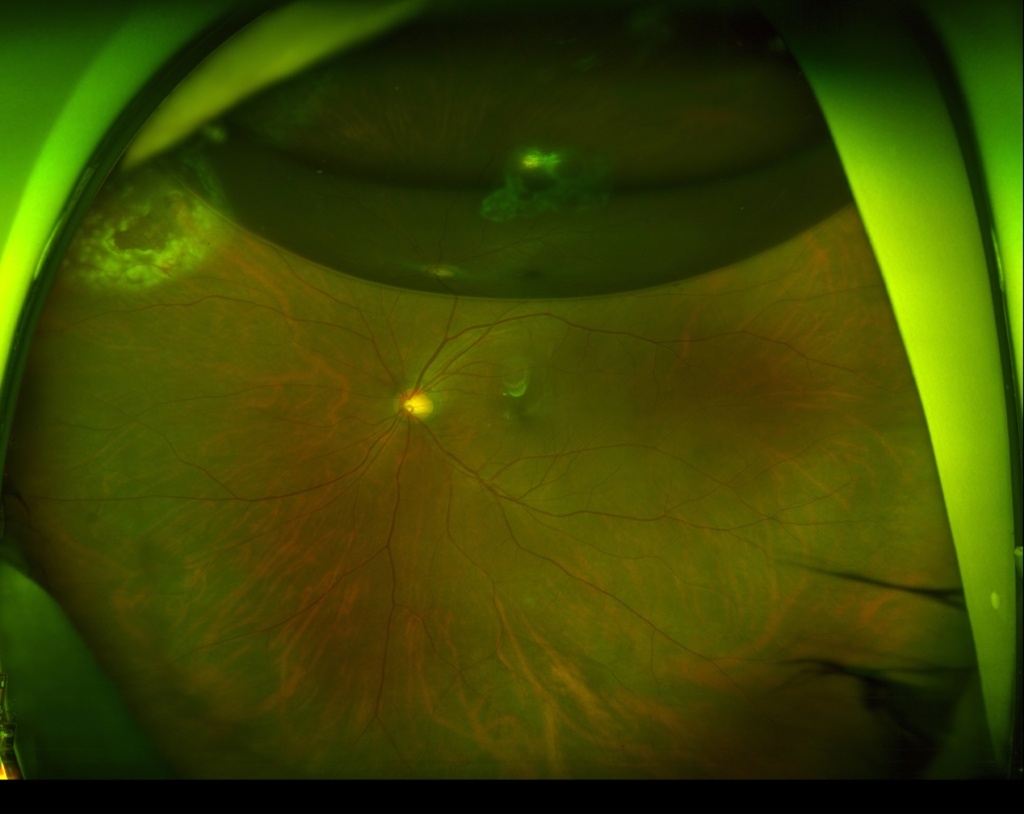

術後1か月

60歳 女性

主訴 10日前から飛蚊症、2日前から視野欠損を自覚

視力 右眼 0.6(1.2×-0.75)

硝子体手術(経毛様体扁平部硝子体切除 Pars Plana Vitrectomy PPV)、眼内レーザー、空気置換)+水晶体再建術を行った。

鼻上側に剥離が剥離があり、格子状変性の耳側縁に馬蹄形裂孔がみられる。

硝子体手術(経毛様体扁平部硝子体切除 Pars Plana Vitrectomy PPV)、眼内レーザー、空気置換)+水晶体再建術を行った。

術後1か月